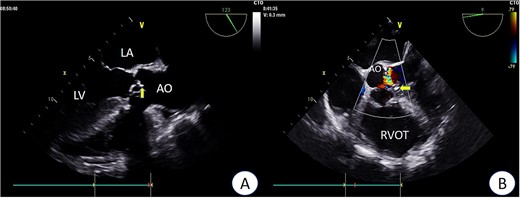

Preoperative TEE revealed moderate calcification, leaflet thickening, and hypertrophy of the tricuspid aortic valve (Fig. 1). The valve leaflets were restricted in motion, with a calculated maximum valve area of ~1.1 cm2 using the continuity equation. Color Doppler flow imaging demonstrated moderate aortic regurgitation. Additionally, a 9 mm-wide ASD was found in the mid-septal region (Fig. 2), with residual lengths on either side. Color Doppler revealed left-to-right shunting at the atrial level.

Preoperative TEE: Aortic valve leaflets, calcification, and regurgitation observed in the short-axis section of preoperative TEE. Key abbreviations: LA - left atrium; LV - left ventricle; AO - aorta; RVOT - right ventricular outflow tract.